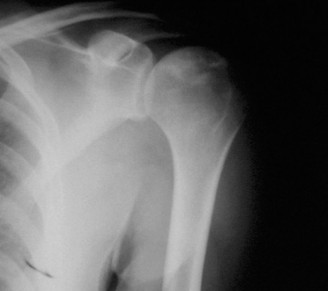

A 17-year-old gymnast presents to clinic with right shoulder pain. She denies any specific injury but reports…

A 28-year-old, recreational athlete presents to your clinic with shoulder pain and a history of multiple subl…